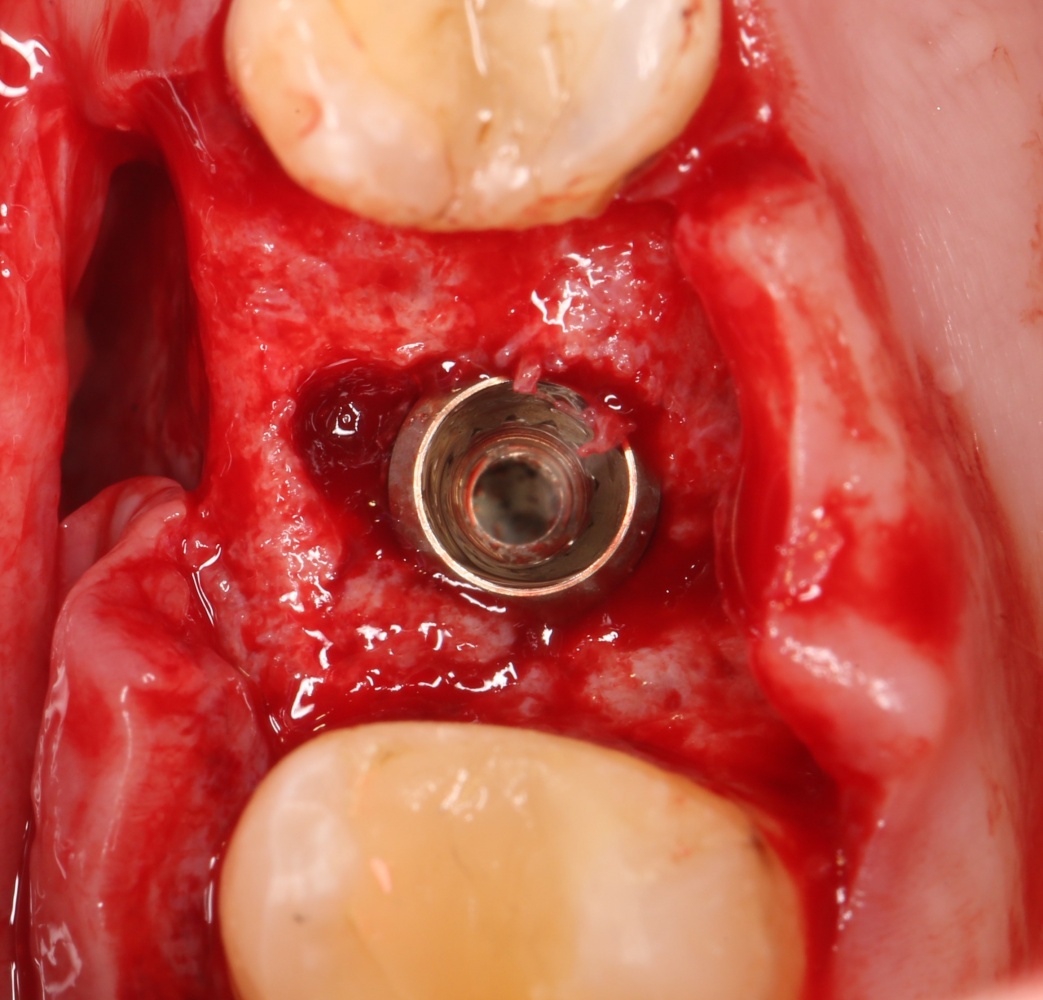

Через 3 месяца — вторая операция — установка имплантата в сформированный объем костной ткани:

Как видите. восстанавливается всё очень легко, никаких дефектов не остаётся, но при этом мы получаем важное преимущество: достаточную свободу движений при формировании субантральной полости и хороший визуальный контроль за состоянием слизистой оболочки. Никакая нажопная оптика или суперпупермикроскоп, к сожалению, не обеспечат подобный контроль при закрытом синуслифтинге. Да, операция получается травматичнее и масштабнее, чем «закрытый» синуслифтинг, но несёт в себе гораздо меньше рисков.